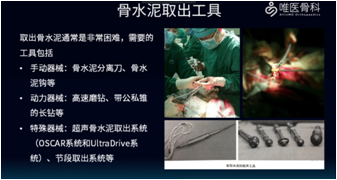

骨水泥取出工具:取出骨水泥通常非常困难,需要的工具包括:①手动器械:骨水泥分离刀、骨水泥钩等;②动力器械:高速磨钻、带攻丝锥的长钻等;③特殊器械:超声骨水泥取出系统(OSCAR系统和UltraDrive系统)、节段取出系统等。

注意:如果有超声骨水泥刀,髓腔水泥的取出将会很容易,所以推荐使用超声骨水泥取出工具。